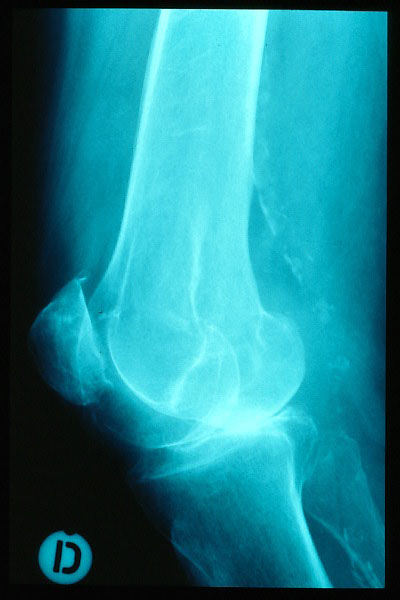

Fractura supracondílea de codo.

Fractura supracondílea de codo.Tras reducción y osteosíntesis.

Fractura supracondílea de codo. Tratamiento con agujas.